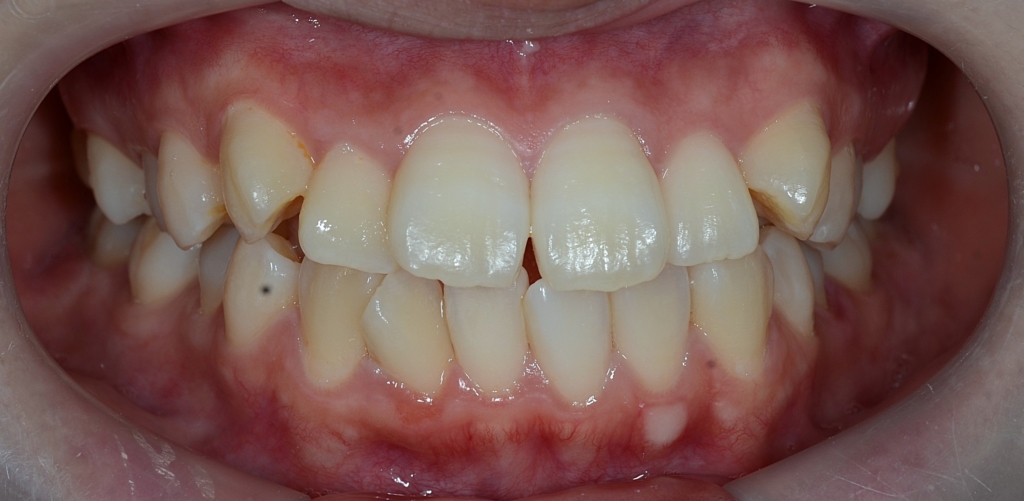

【Before】

この患者さんの場合、

#1.歯と顎の不調和による叢生(軽~中等度)

と診断しました。